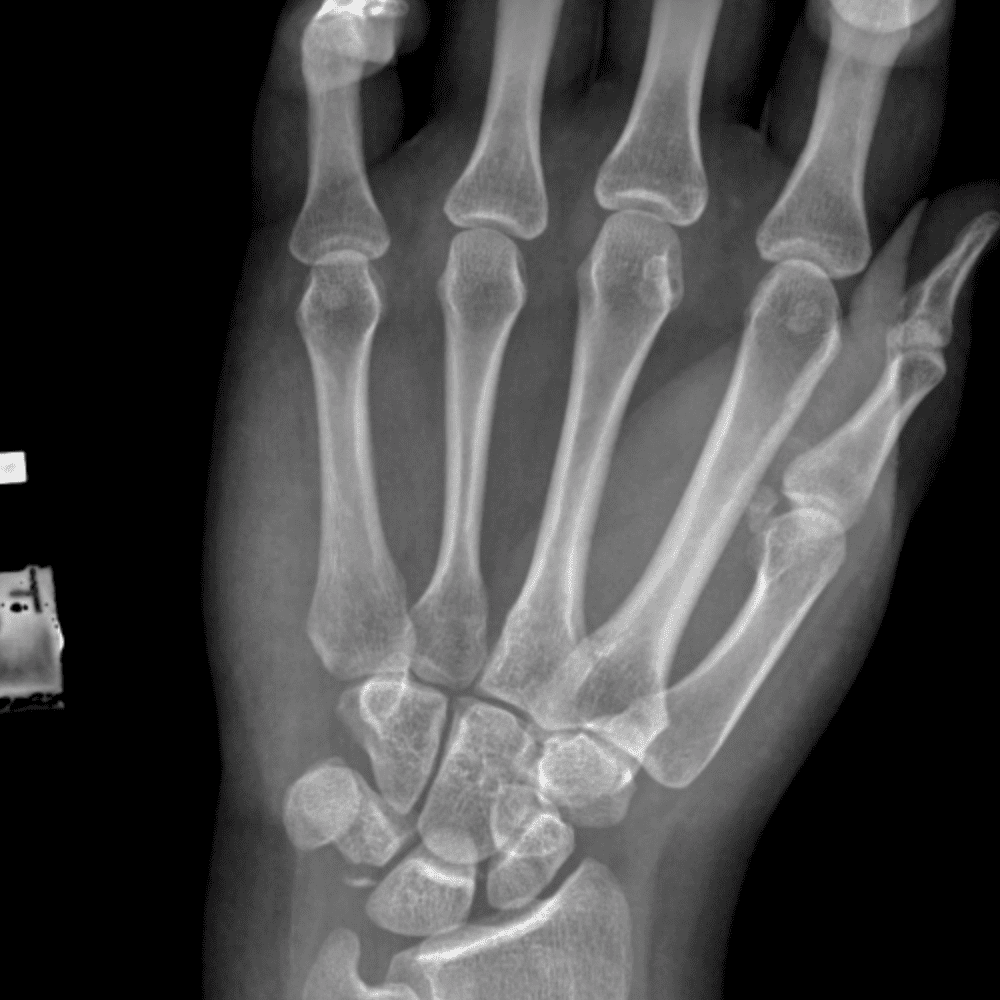

Simulates call by including subtle or difficult cases and some normals.

30 cases